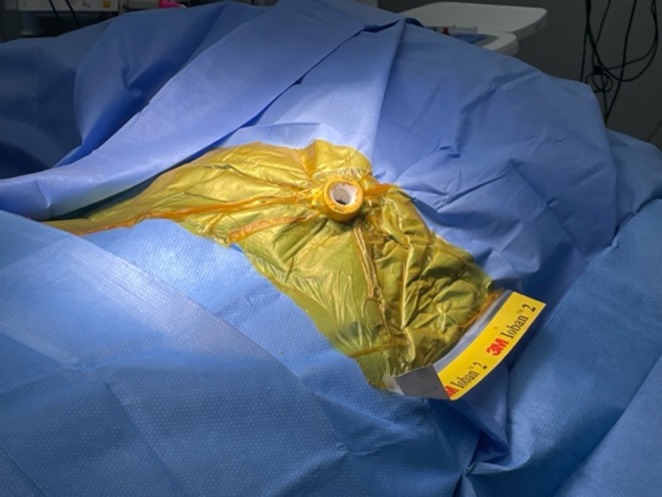

To proceed with TG‐ERCP, the roux limb and gastric remnant were both identified and dissected. The gastric remnant was mobilized, and an abdominal wall incision was made in the upper left quadrant above the left extension of the Mercedes incision. A gastrotomy was made, and a 15 mm trocar was placed through it into the gastric lumen, as previously described (Figure 2) [ref. 14]. The anterior wall of the remnant was then stammed to the abdominal wall with a 3–0 barbed suture. The abdominal cavity was temporarily closed, and overlying drapes were placed, allowing access solely to the 15 mm trocar (Figure 3). The advanced endoscopist then cannulated the trocar with the side‐viewing endoscope, and an ERCP was performed in the usual fashion (Figure 4). A single biliary stricture was identified at the anastomosis, and a 10 cm, 7‐French plastic stent was placed across (Figure 5). No balloon dilation of the anastomosis was performed due to the recentness of the anastomosis. The trocar and the overlying drapes were removed, and a 24‐French gastrostomy tube (G‐tube) was placed through the gastrotomy for future biliary access and enteral nutrition, if deemed necessary. Liver biopsy was performed that demonstrated marked canalicular cholestasis and bile ductular proliferation consistent with the biliary obstruction. There was no evidence of rejection.